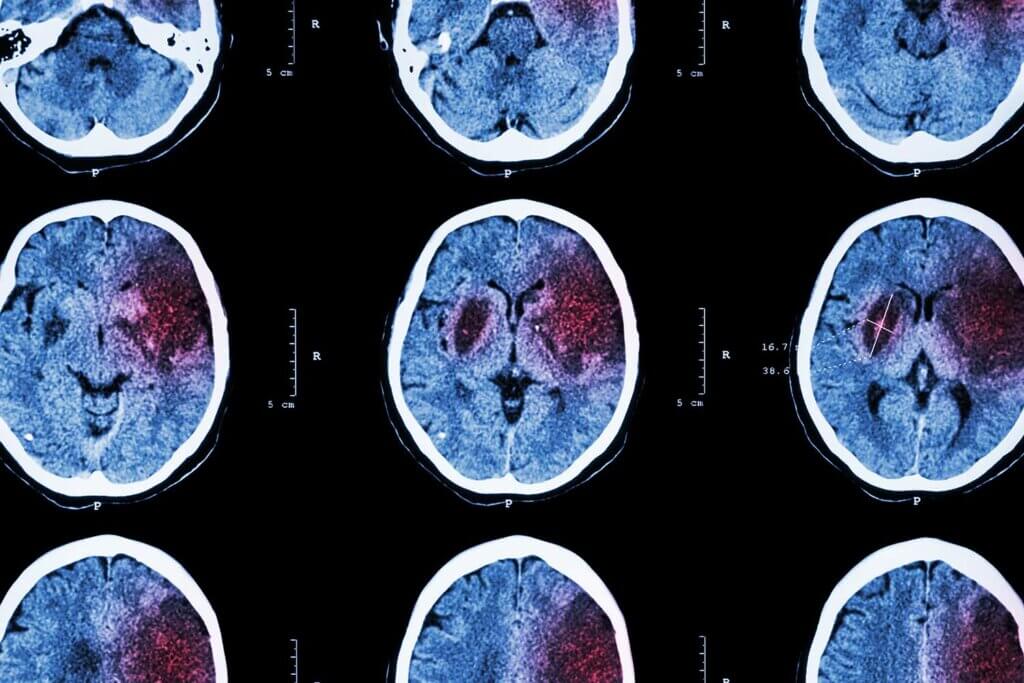

Traumatic Brain Injury (TBI)

The most common causes of traumatic brain injuries are falls, gunshot head wounds, car crashes, and assault.

Some 64,000 TBI-related deaths yearly, but a traumatic brain injury can also result in long-term disability. Therefore, rapid medical treatment is vital to reduce the risk of death and disability.

traumatic brain injury top time sensitive medical emergencies